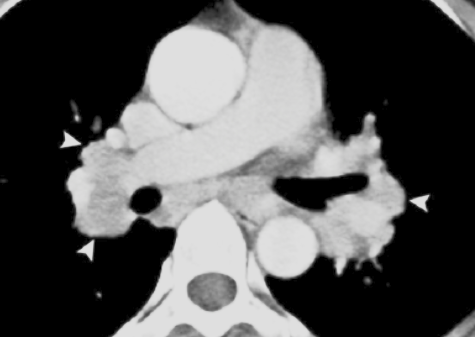

Bilateral enlargement of hilar nodes occurs in: triad

• Sarcoidosis-2 : The diagnosis is almost certain if the hilar enlargement is symmetrical and if the patient is asymptomatic, or has either erythema nodosum or iridocyclitis. Enlargement of the right paratracheal nodes is common. Lung changes are sometimes visible.